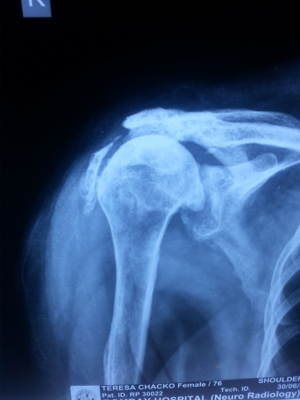

Pre Surgery X-ray for Rotator Cuff Arthopathy

Pre Reverse Shoulder Replacement